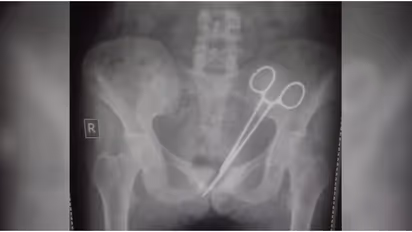

ശസ്ത്രക്രിയയിലൂടെ പുറത്തെടുത്ത ഏഴ് സെന്റിമീറ്റർ നീളമുള്ള കത്രിക ശാസ്ത്രീയ പരിശോധനയ്ക്ക് അയയ്ക്കും. കത്രികയുടെ കാലപ്പഴക്കം കണ്ടെത്തുക നിർണായകമാണ്. നിലവിൽ ഉഷയുടെ ആരോഗ്യ നില തൃപ്തികരമാണ്. സ്വകാര്യ ആശുപത്രിയിൽ ഐസിയുവിൽ നിരീക്ഷണത്തിൽ തുടരുകയാണ് ഉഷ.